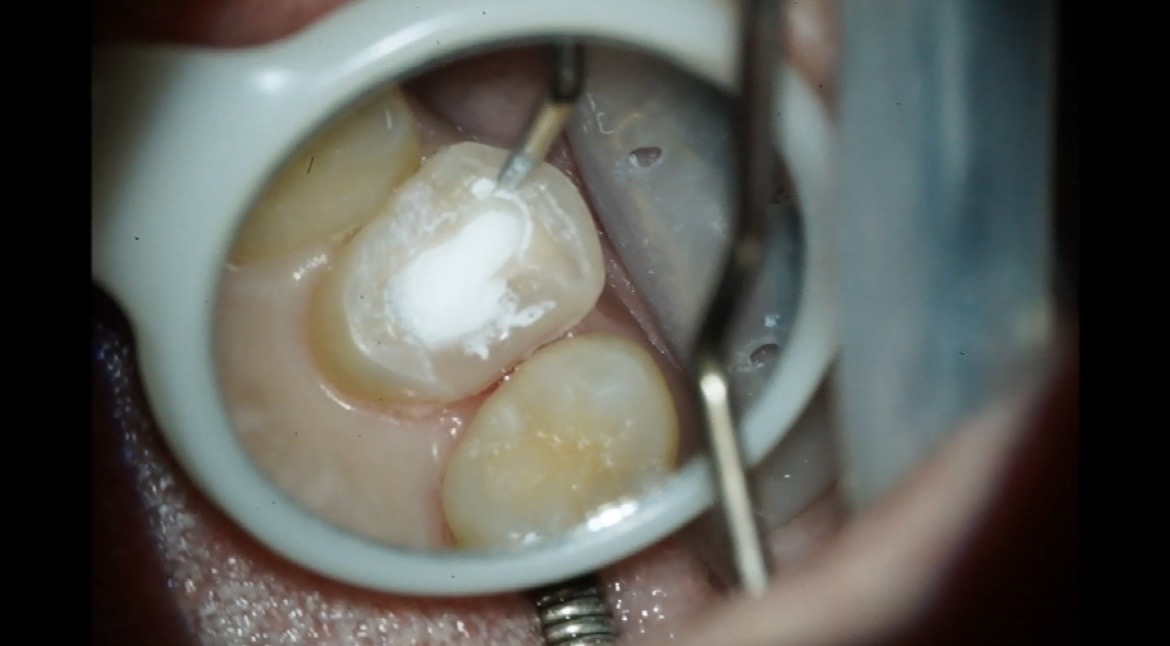

今回の症例では過去に虫歯治療を行い2次カリエスによりMTAセメントを使用し治療された方の紹介になります🦷

【右上第一小臼歯】

【処置前】削る前→虫歯除去

削ると歯と歯の間から虫歯が進行し、まだ虫歯が残ってる状態になります。

MTAセメント詰めた後↓ ↓ ↓